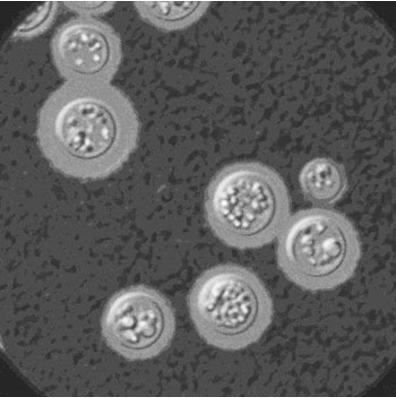

To answer this question, the Hargarten Lab studies human infections caused by the fungus Cryptococcus.

Worldwide, this fungus is breathed into the lungs of people enjoying the outdoors and rapidly cleared by a robust immune system. In rare cases, the fungus persists in the host, resulting in pulmonary infections and meningitis. It is now the most common cause of non-bacterial meningitis in the US. Worldwide, it kills 180,000 annually and leaves scores more with debilitating neurological sequelae despite adequate antifungal treatment. Think “The Last of Us,” but without the zombies.

The goal of the Hargarten Lab is to define the host factors critical for protection against Cryptococcus and to develop personalized therapeutic approaches for susceptible patient populations to correct deficits found in these host factors.